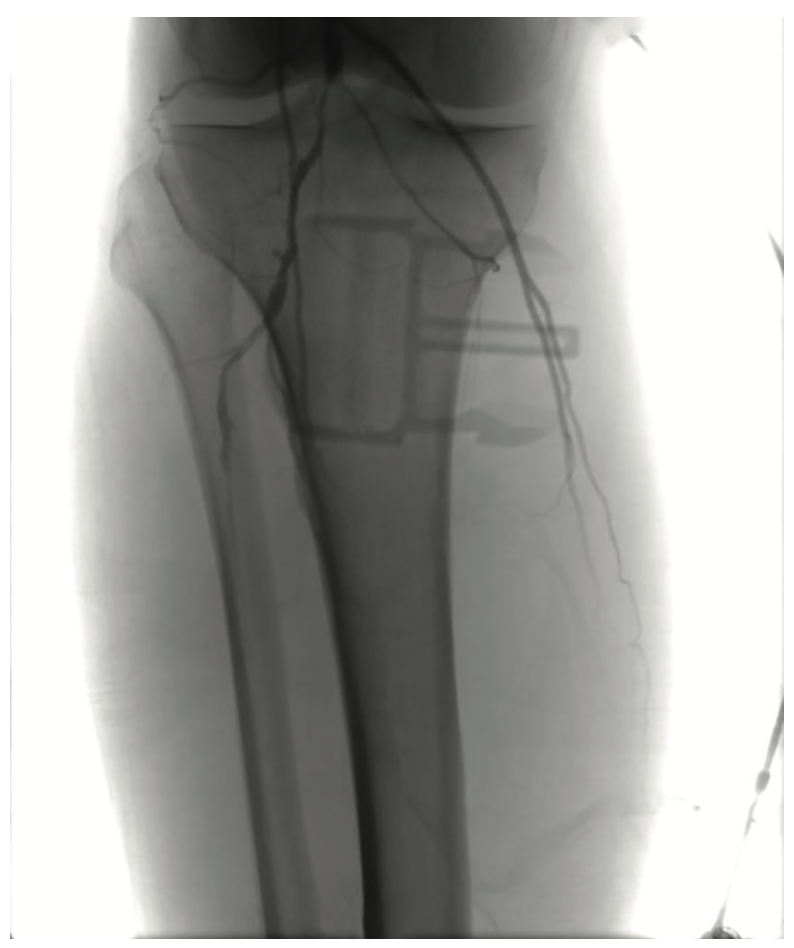

As previously planned, the patient returned two weeks after treatment of the right leg for treatment of his left leg. This procedure was markedly similar in both disease pattern and intervention to the previous one. Baseline angiography of the left leg also revealed patent iliac, common femoral and profunda arteries, moderate inflow disease of the SFA, and significant disease in the AT, TPT, and PT arteries (Figure 6):

• Distal SFA: 60%-70% stenosis

• AT: 99% stenosis

• TPT: 99% stenosis

• PT: 100% stenosis

Following optimization of the inflow disease, a 3 mm x 120 mm Serranator balloon was used with overlapping, sequential inflations up to 8 atm in the AT artery. The same balloon was then utilized in the TPT at a maximum of 6 atm (Figure 7). Both AT and TPT lesions had 0% stenosis and no dissections, perforations, or recoil were observed (Figure 8).